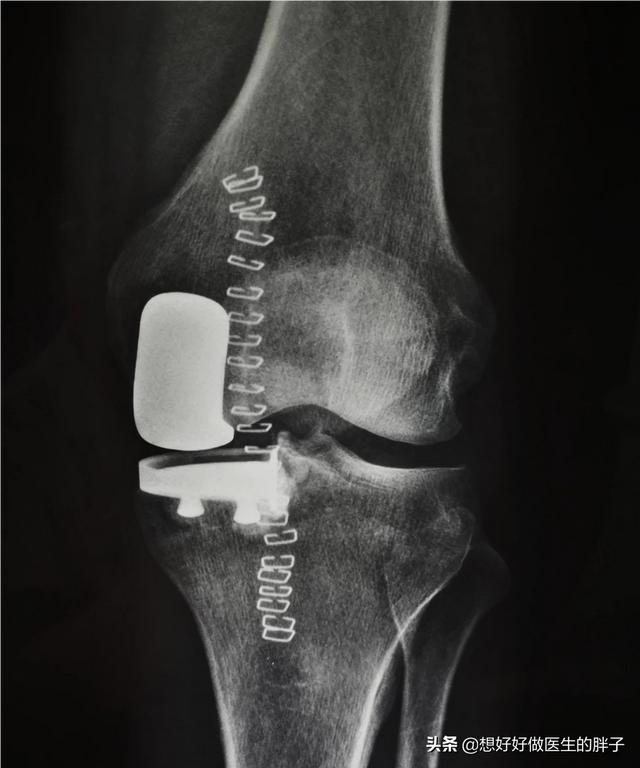

晚期骨关节炎:晚期骨关节炎由于患者已经出现了明显的关节畸形,很多患者已经谈不上生活质量,被折磨的痛不欲生,那么此时可能进行手术治疗的办法是最好的措施。过去主要采取的办法是比较单一的,我们称之为全膝关节表面置换术,也就是像膝关节软骨已经磨损殆尽的表面替换成金属表面,关节内的骨骼就不会发生直接的摩擦,疼痛也就会消失。

但是在常年的手术经验积累当中,很多医生也发现,部分患者仅仅是内侧的膝关节或者是外侧的膝关节问题比较严重,而针对某一侧的关节问题将整个关节的表面全都置换掉,确实有些可惜。所以目前也开展了单髁置换手术以及模块化的置换手术,我们统称为部分关节置换术。